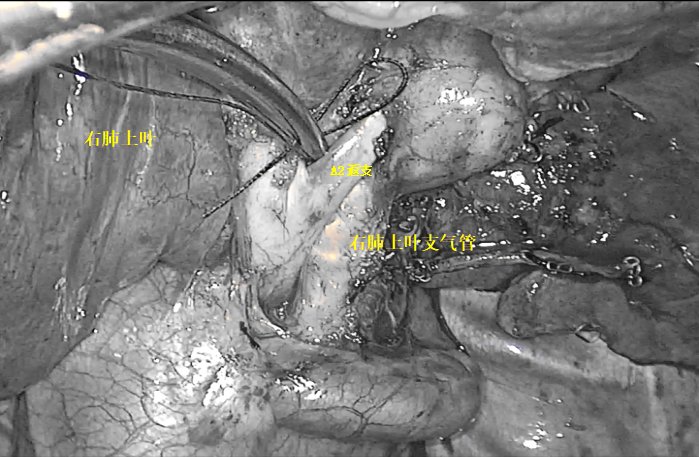

对李女士的病情,赵宏光主任团队高度重视,在吴毓优主任医师、刘运仲副主任医师的配合下,赵宏光主任精准阅片,分析肺段结构后,决定为其行胸腔镜下右上肺后段切除术。

术前,赵主任团队分析肺段动脉、静脉及支气管,并准确定位结节位置,精准分析切除范围,制定肺段切除计划。术中,由于李女士叶间裂发育不全,给后段切除手术造成了一定阻碍,但赵宏光主任凭借着坚实的解剖知识及高超的手术技巧和丰富的手术经验,清晰地将各个结构分离并离断各支肺段动脉、静脉及支气管,精准地切除右上肺后段。